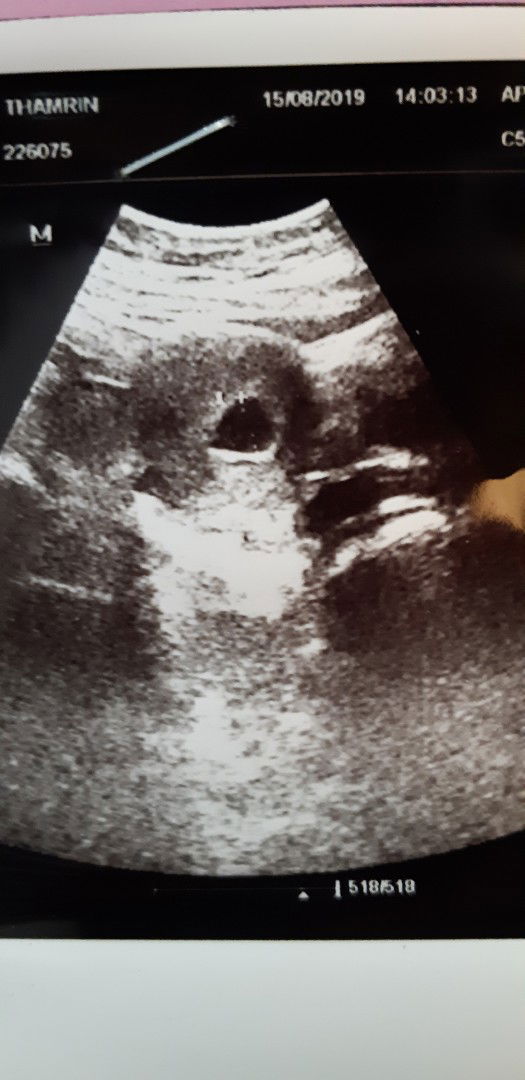

usg di usia 6 minggu, belum ada kelihatan

Halo bunda saya mau bertanya di usia 6 minggu belum ada kelihatan apa apa, apa ada yg seperti aku??? Apa emang kayak begini? Aku worry banget, karna anak pertama. Info dongggg bunda bunda sekalian